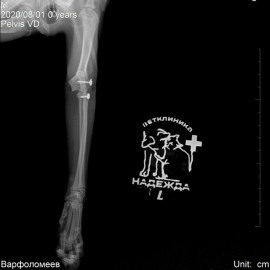

Котик Персик после покуса собаки. Обратились с жалобами на отсутствие опороспособности на левую переднюю и задние лапы. После рентгенографического исследования поставлен диагноз: вывих левого локтевого сустава, перелом костей правого крестцово-подвздошного сочленения, перелом лонной и седалищной костей таза. Проведена операция: остеосинтез левого локтевого сустава, остеосинтез правого крестцово-подвздошного сочленения таза.

Снимки 3-5 после операции